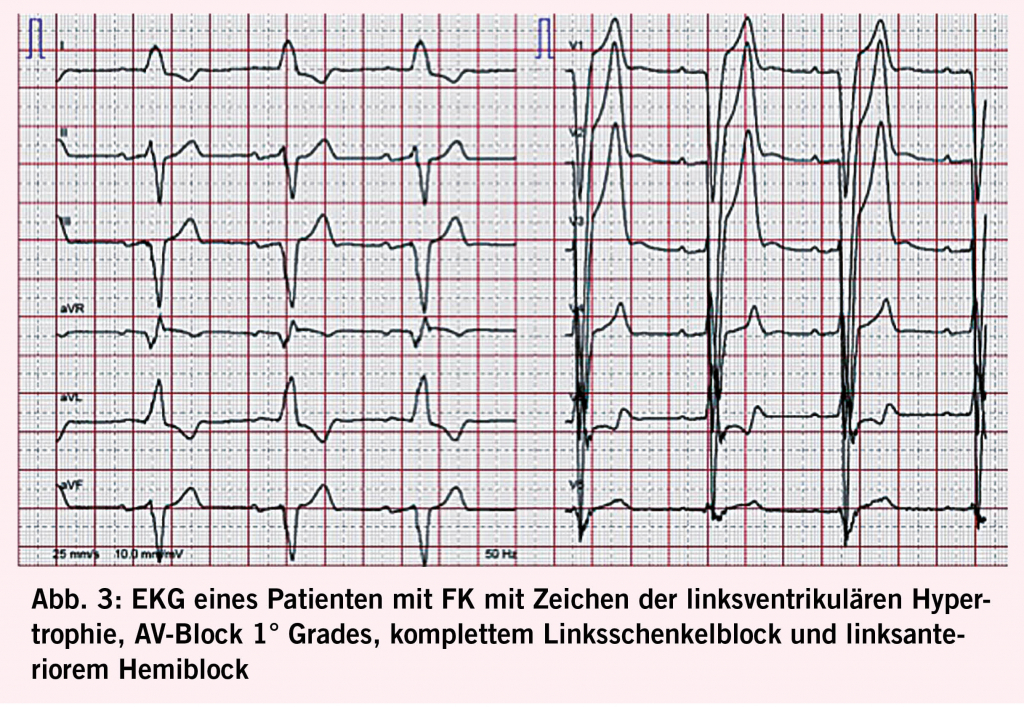

Das Herz ist mit 68% das Organ mit der häufigsten intrazellulären GB3-Akkumulation (10,11), die in den Myozyten, Herzklappen und Gefässendothelien stattfindet und neben der Infiltration auch einen inflammatorischen und oxidativen Stress verursacht (12). Als Folge leiden über die Hälfte der männlichen Fabry-Patienten und 18- 28% der Frauen mit Morbus Fabry (13, 14) unter einer konzentrischen LVH (siehe Abb. 2) mit einer typischerweise früh einsetzenden diastolischen Dysfunktion (15,16) und im Verlauf restriktivem Füllungsmuster (17, 18). Die LVH bei Fabry unterscheidet sich in der Regel durch das Fehlen einer Ausflussobstruktion von einer idiopathischen hypertrophischen Kardiomyopathie (4) und kann auch mit einer rechtsventrikulären Hypertrophie und Dysfunktion einhergehen (19). Während bei Männern erste kardiale Beschwerden mit durchschnittlich 33 Jahren einsetzen, wurde bei Frauen ein späterer Beginn um das 40. Lebensjahr beobachtet (7). Typischerweise kommt es im Verlauf zu einer Herzinsuffizienz mit erhaltener Ejektionsfraktion (7). Aufgrund der Endothelablagerungen kann es zudem oft auch zu einer endothelialen Dysfunktion (20, 21) kommen. Möglich ist auch eine mikrovaskuläre Dysfunktion, die Angina pectoris verursacht (22). Die fortgeschrittene Fabry-Kardiomyopathie (FK) ist durch eine fibrotische Umwandlung des linken Ventrikels, die typischerweise infero-baso-lateral beginnt und nach transmural fortschreitet, gekennzeichnet (23). Diese Fi-broseareale können Rhythmusstörungen (siehe Abb. 3), darunter Sinusbradykardien, höhergradige AV-Blockierungen, und Kammertachykardien hervorrufen und infolge zum plötzlichen Herztod führen (24-26). Auch Vorhofflimmern ist bei Fabry-Patienten häufig zu finden, wobei die Inzidenz vier Mal so hoch ist wie in der Normalbevölkerung, bei über 50-jährigen Patienten sogar zwölffach erhöht (25). Bei der fortgeschrittenen FK kommt es gelegentlich auch zur Herzklappenschädigung, insbesondere zur Insuffizienz der Aorten-, Mitral- oder Trikuspidalklappe (24) sowie Erweiterung der Aortenwurzel (27). Eine weitere typische Veränderung ist ein prominenter Papillarmuskel (28) (Abb. 2).

Die transthorakale Echokardiografie ist die primäre und am leichtesten verfügbare Methode zum Screening und zur Verlaufsbeurteilung bei FK (Abb. 2). Sie ermöglicht es jedoch nicht, eine Fabrykardiomyopathie von anderen Hypertrophien abzugrenzen und eine Herzbeteiligung vor Beginn der LVH zu erkennen. Letzteres ist gerade bei Frauen relevant, da diese eine Myokardfibrose oft noch vor den Zeichen einer LVH entwickeln (29). Insgesamt haben mittlerweile 60% der Patienten bei der Diagnosestellung noch keine nachweisbare LVH (30). Durch den Einsatz neuerer Techniken (z.B. Strain Analyse und 2-D Speckle Tracking) können jedoch myokardiale regionale Unterschiede sowie eine beginnende diastolische Dysfunktion vor der LVH detektiert werden (14, 31). Den Goldstandard für die Beurteilung struktureller Veränderungen bei Morbus Fabry sowie die Feststellung von Myokardfibrosen stellt die kardiale Magnetresonanztomographie (CMR) dar. Sie ermöglicht 1. mittels «Late Gadolinium Enhancement» eine frühzeitige Erfassung von Fibrosearealen (16, 32), was von grosser prognostischer Bedeutung ist, da deren Vorhandensein und Ausmass mit dem Risiko des Auftretens potentiell lebensbedrohlicher Rhythmusstörungen korreliert (33) und bei der Indikationsstellung zur ICD-Implantation helfen kann (34), 2. mittels nativem T1 Mapping mit hoher Spezifität und Sensitivität eine FK von anderen Kardiomyopathien zu differenzieren (sehr niedriger T1 Map Wert) (19, 32, 35), und 3. Verlaufskontrollen des Remodelings unter ERT durchzuführen (10, 36). Bei Kontraindikationen für eine CMR kann die Frage nach einer mikrovaskulären Dysfunktion auch alternativ mittels kardialer Positronen-Emissions-Tomographie untersucht werden (37). Im Ruhe-Elektrokardiogramm (EKG, siehe Abb. 3) lassen sich oft charakteristische Veränderungen wie ein positiver Sokolow-Lyon-Index und präkordiale T-Wellen-Negativierungen sowie gelegentlich auch eine PQ-Zeit-Verkürzung und QTc-Zeit-Verlängerung feststellen (38). Bei allen Patienten mit Symptomen sowie bei bekannter Myokardfibrose sollte regelmässig ein Holter-EKG durchgeführt werden. Bei unauffälligem Holter-EKG und persistierendem Verdacht auf eine seltener auftretende HRST sollte die Implantation eines Event Recorders erwogen werden (39). Als Verlaufsparameter, der mit dem Fibrosegrad und dem Schweregrad der FK korreliert, kann hs-Troponin eingesetzt werden (40).